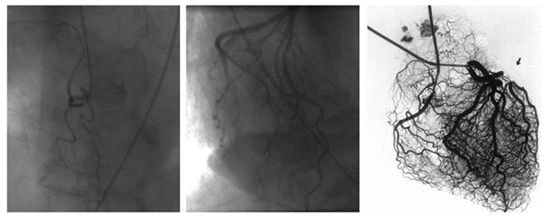

一般认为冠脉造影只能看到直径>0.4-0.5 mm的大血管。就像下面这张图的左边。